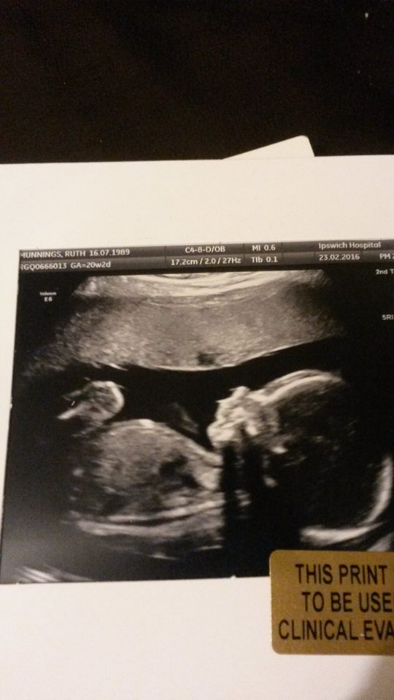

Our son at twenty weeks.